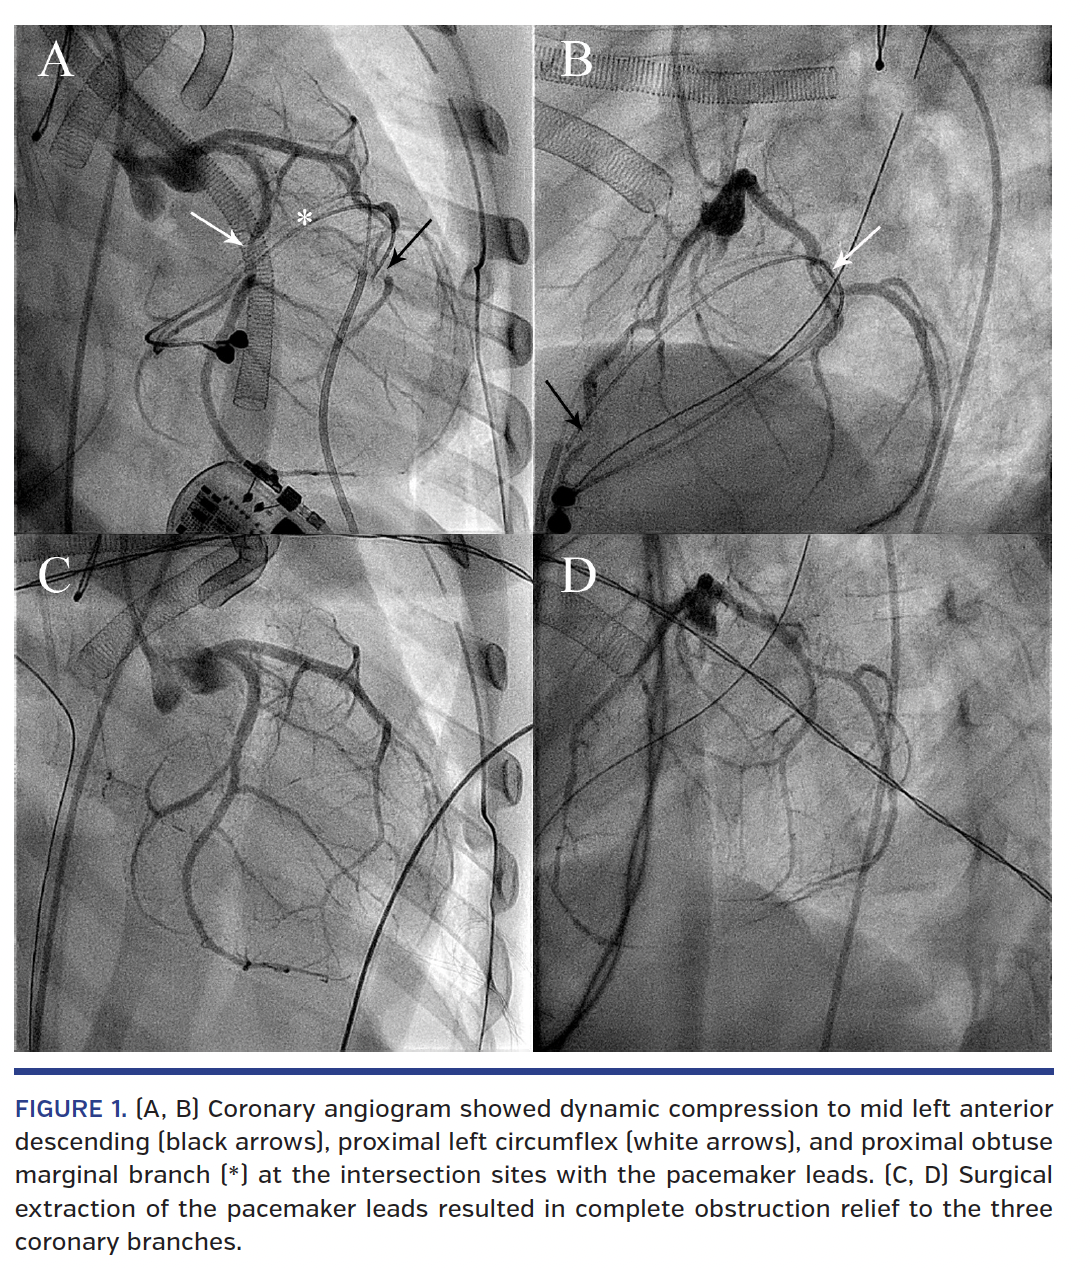

A 6-year-old girl with a permanent epicardial pacemaker implanted in infancy for congenital complete heart block received generator change. Immediately post procedure, she had ventricular tachycardia with refractory cardiac arrest. Central extracardiac membrane oxygenation was inserted. Echocardiogram revealed severe left ventricular dysfunction. Coronary angiogram showed dynamic compression (Figures 1A and 1B; Videos 1 and 2) to the mid left anterior descending coronary artery, the proximal left circumflex artery, and the proximal obtuse marginal branch at the intersection sites with the pacemaker leads. Surgical extraction of the pacemaker leads resulted in complete obstruction relief to the three coronary branches (Figures 1C and 1D; Videos 3 and 4), confirming the diagnosis of mechanical compression by the pacemaker leads to the coronary arteries.